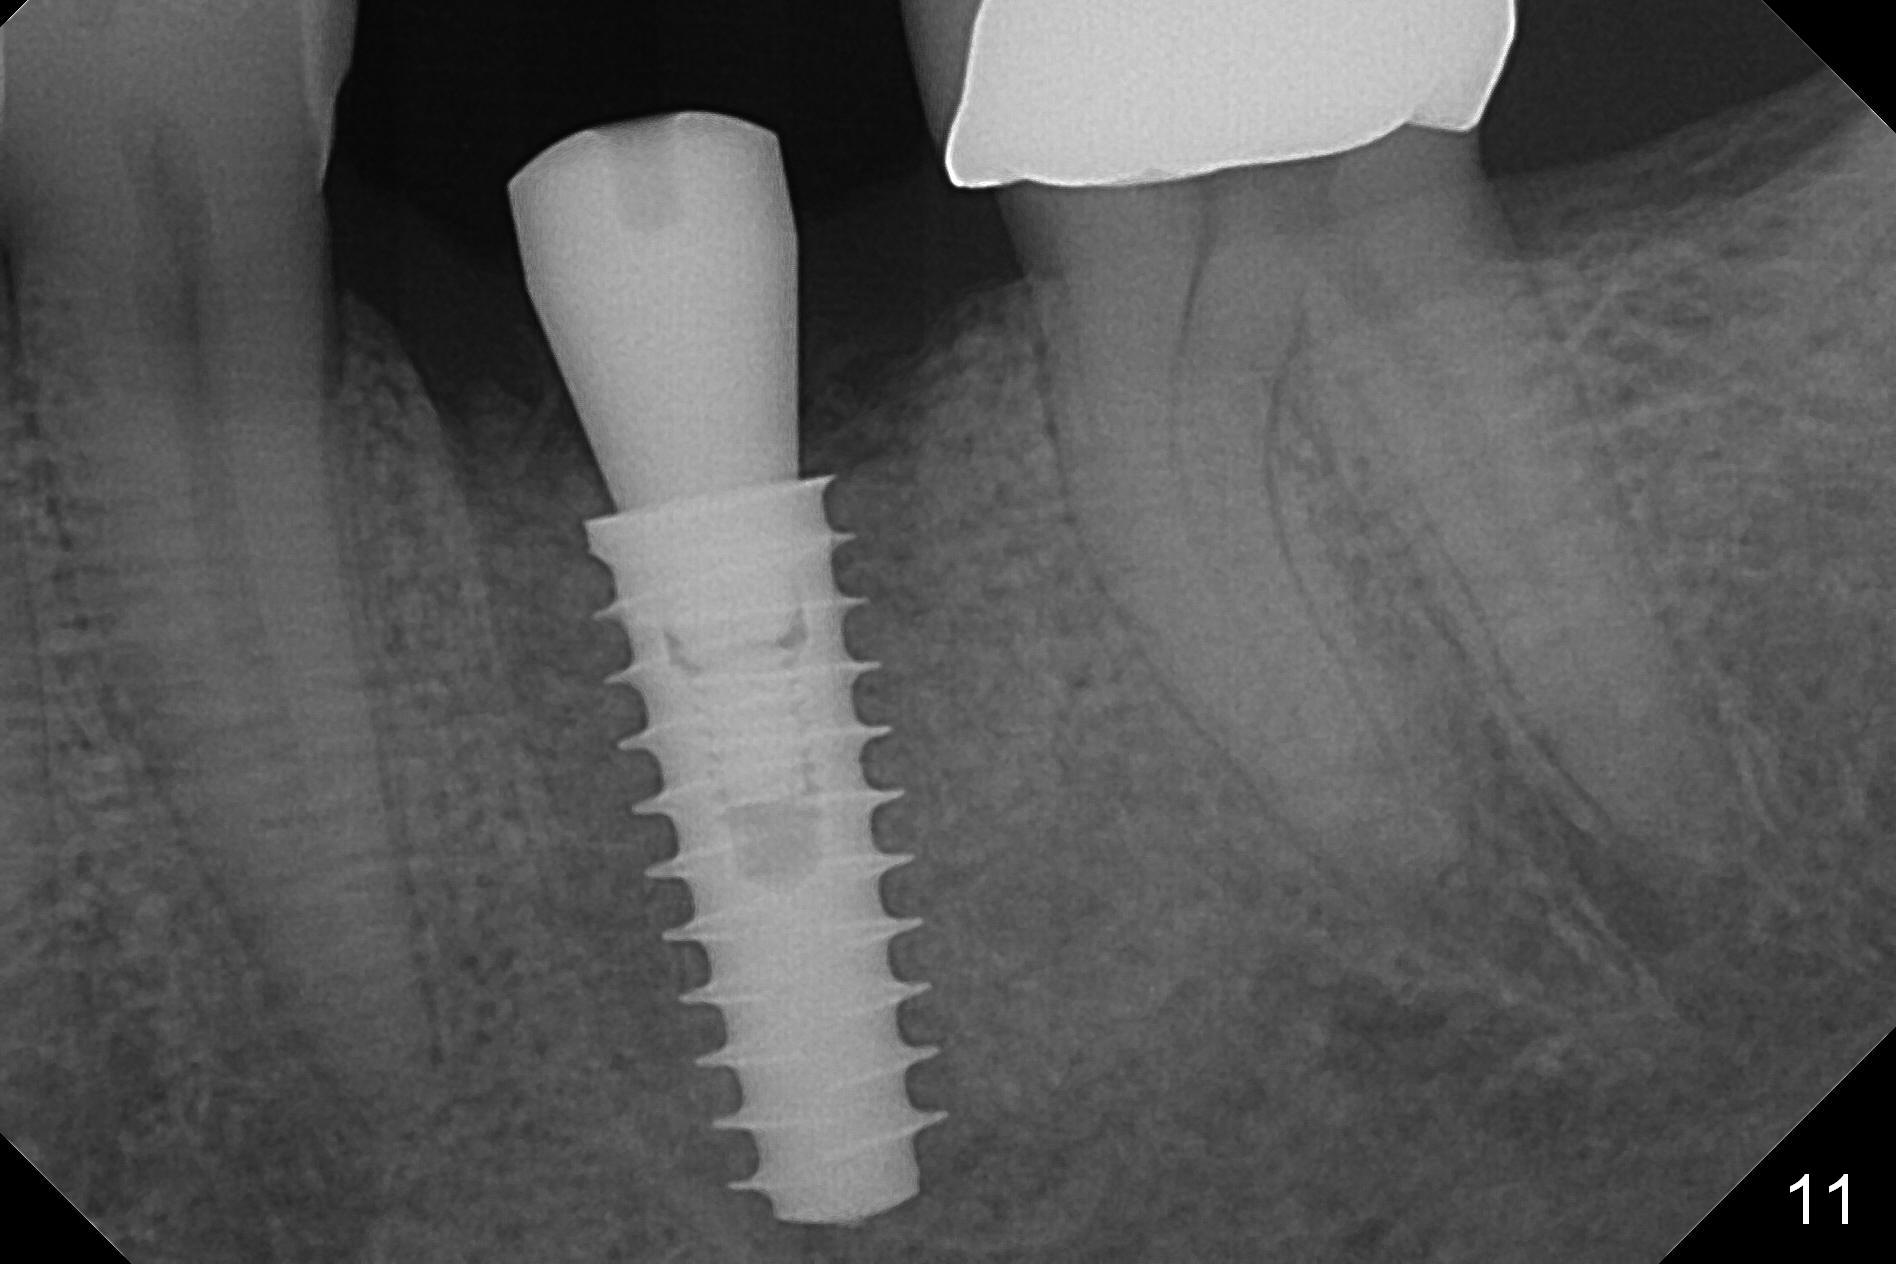

The tooth #19 is easy to get loose, but it cannot be luxated. After sectioning and extraction (Clindamycin), the septum is found to be thin (Fig.4). A surgical fissure bur is used to initiate osteotomy, followed by 1.6 mm pilot drill. It is difficult to use Marking bur (wobbling over the basically pointed septum). It is impossible to use 4.3 mm Magic Drill (MD, one drill system), since it jumps. The smallest MD has to be used (2.8 mm). When the next drill (3.3 mm) is being used for 13 mm with stopper (Fig.5), the patient experiences transient pain. The depth is suggested from the design in Fig.2. The thin septum appears not to be a reliable landmark. When block anesthesia is administered, the initial depth should be shortened. The drill appears to be close to the Inferior Alveolar Canal (Fig.5). Then the depth changes to 11 mm with the following drills (3.8 and 4.3). The mesial and distal walls of the septum are gradually perforated. A 5x9 mm dummy implant is placed only after using 4.8 mm drill (Fig.6). The implant appears to be short. When a longer implant is placed (5x11 mm), it does not easily enter the osteotomy, either sliding into the mesial or distal socket with the implant separating from the implant driver. It appears that a premount implant is appropriate in this situation. When the 5x11 mm implant is finally seated with stability, it is 6 mm apical to the gingival margin. The longest cuff of IBS abutment is 4 mm. A longer implant is needed (Fig.7, 5x13 mm). Placement is not easy as mentioned above. Insertion torque is <20 Ncm when the patient experience a little discomfort. A 6.5x4(4) mm pair abutment is placed (A), apparently proper for restoration. Allograft is placed (Fig.8 *) prior to immediate provisional. The patient complains of bad smell from the site 24 days postop. When the provisional is removed, the abutment is found to be mobile. When the latter is removed with local anesthesia, bone graft granules are attached to the socket above the lightly mobile implant (Fig.9). In fact the latter appears to be stable after a few turns by finger. A healing screw is placed; the socket is closed with collagen plug and 4-0 Chromic gut sutures (Fig.10). It appears that a larger implant should have been used to achieve higher torque. Two months later (3 months postop), the coronal end of the implant is partially exposed. A 5x4 mm healing abutment is placed. It appears that the implant is stable. The implant appears to have osteointegrated 4 months postop (Fig.11). Impression is taken.

The gingiva looks healthy 8 months postop (3 months post cementation (after abutment screw retightening and addition of porcelain to proximal surfaces, Fig.12). New bone has apparently covered the implant plateau (Fig.13 arrows). Bone density between threads increases 9 months post cementation (Fig.14). There is 2 mm bone superior to the implant plateau mesial and distal 1 year 9 months post cementation (Fig.15,16). The crown/abutment is loose 3 times (3 months (Fig.14), 11 months (between Fig.14 and 15) and 2 years 3 months post cementation). In spite of being stable 3 years 10 months post cementation, a smaller abutment is placed (Fig.17 (PA), 18 (BW)) with impression for a new crown. After intraoral cementation, the new crown/abutment is removed for residual cement removal. When the complex is reseated, it is not smooth, probably due to proximal undercut. Fortunately the abutment appears to be completely seated, followed by 20 Ncm torque (Fig.19).